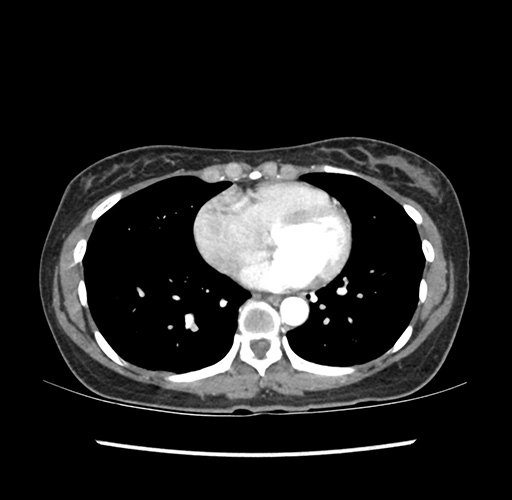

Imaging Analysis

Look through the patient's CT scan to identify any areas of concern for the necessary procedure.

Based on your CT findings, which issue(s) would give reason for "planned slowing down moment(s)" in this case?

Considering a standard left lateral sectionectomy procedure, what step(s) of the operation would you do differently in this case ?